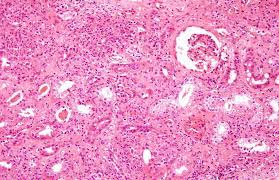

El signo patológico típico de la nefritis intersticial es la respuesta inflamatoria intersticial con edema y posible daño de células tubulares.